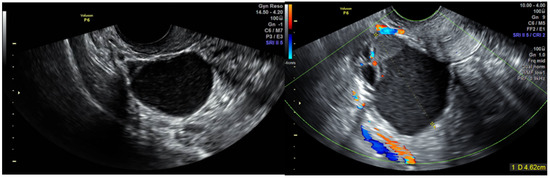

| 6 | 22 | 0 | Left | 46 | Multilocular solid cyst with papillations | Yes | Uterosacral ligament nodules | Hydrosalpinx | 22 | Normal follow-up, no recurrence. |